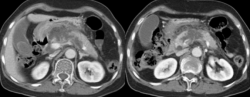

1腺炎CT表现:多数有胰腺弥漫性增大,少数轻者表现正常;密度正常或略减低,均匀或不均匀;胰腺轮廓清楚或模糊,渗出明显者可有胰周积液;肾前筋膜及肾周筋膜增厚;增强扫描胰腺均匀强化。

截屏2022-10-06 18.52.50截屏2022-10-06 18.53.15

肾旁前间隙、肾后间隙积液

截屏2022-10-06 18.53.51

腺炎MRI表现:胰腺局限/弥漫肿大,呈T1低信号、T2高信号;胰腺轮廓清楚或模糊,渗出明显者可有胰周 或胰外积液,呈T1低信号、T2高信号;合并出血,T1T2皆呈高信号;增强扫描:水肿型,胰腺均匀强化 ;坏死型,胰腺不均匀强化,坏死区无明显强化。

截屏2022-10-06 18.55.47